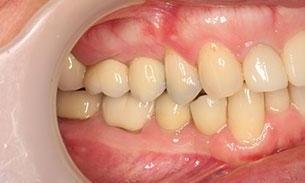

This man in his 50s was unhappy with the amalgam filling used to fix cavities. After discussing options, we agreed to fix his appearance by putting crowns on the teeth which create more of a natural look. This patient was very happy with the end result and is now in maintenance mode.